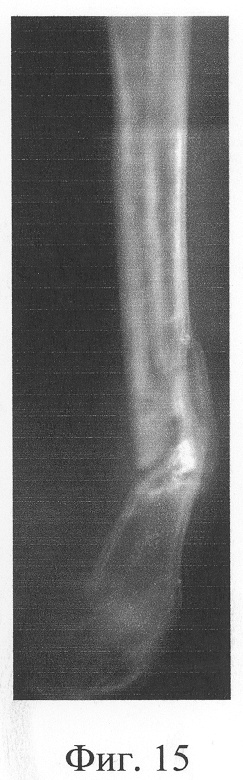

Больная П., 42 лет, поступила для оперативного лечения с диагнозом «атрофические ложные суставы обеих большеберцовых костей; сросшийся с укорочением 5 см перелом левой бедренной кости, хронический остеомиелит левой бедренной кости, фаза ремиссия; посттравматическая невропатия правого малоберцового нерва». В анамнезе – накостный, а затем дважды внеочаговый остеосинтез левой большеберцовой кости с исходом в ложный сустав; 4 операции внеочагового остеосинтеза правой большеберцовой кости, в том числе с костной пластикой; сроки фиксации в аппарате от 5 до 10 мес. Результат не достигнут: с обеих сторон сформировались ложные суставы (фиг.8-11 – клинические и фиг.12-15 – рентгенологические данные до лечения по предложенному методу).

Одномоментно выполнены операции: резекция ложных суставов обеих большеберцовых костей, резекция левой малоберцовой кости, комбинированный чрескостный остеосинтез костей обеих голеней, костная пластика ложных суставов деминерализованным костным аллотрансплантатом из трубчатой кости, предварительно в лабораторных условиях заселенным аутологичными мезенхимными стволовыми клетками, выделенными из костного мозга пациентки, с плотностью заселения 7-10 млн на 1 см3 трансплантата. В послеоперационном периоде потребовалась дополнительная коррекция положения фрагментов на правой голени, что привело к смещению трансплантата из костного паза. Дренажи удалены на 3-е сутки, швы сняты на 15 сутки, антибактериальная терапия под контролем клинического фармаколога с учетом анамнеза. Ходьба с дополнительными средствами опоры с 7 суток послеоперационного периода. Компенсация укорочения бедра обувью (фиг.16-17 – клинические и фиг.18-19 – рентгенологические данные в процессе лечения, трансплантаты отчетливо видны на рентгенограммах, отмечается нарастание плотности костной ткани в области трансплантатов).